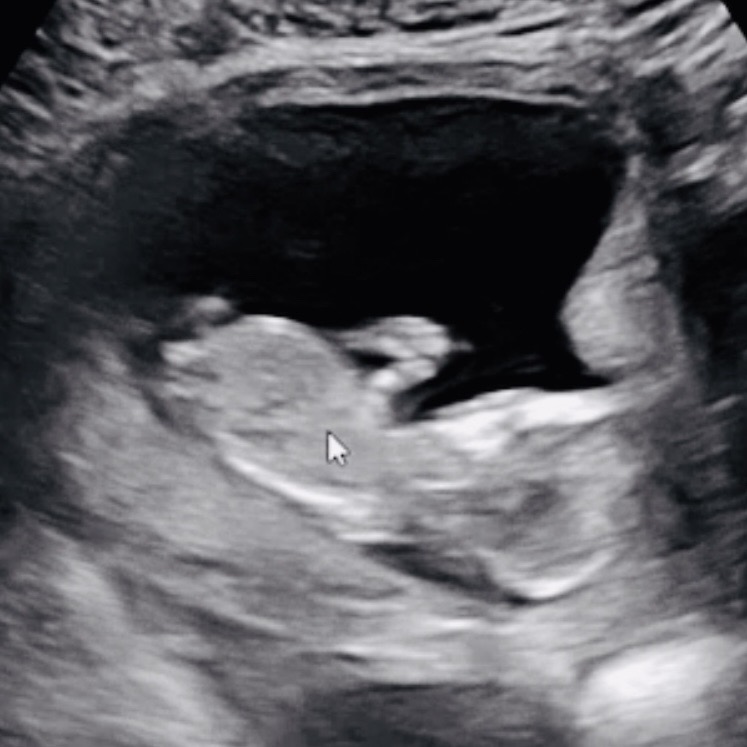

오늘이 딱 12주차 되는날이라 초음파보고왔어요!! 각도법 볼지를 몰라서ㅠㅠㅠ 맘님들이 보시기엔 딸일까요! 아들일까요!